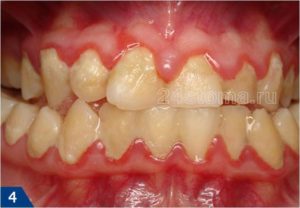

Вид больных и протезированых зубов, вы хотите себе такие зубы уже в молодом возрасте.